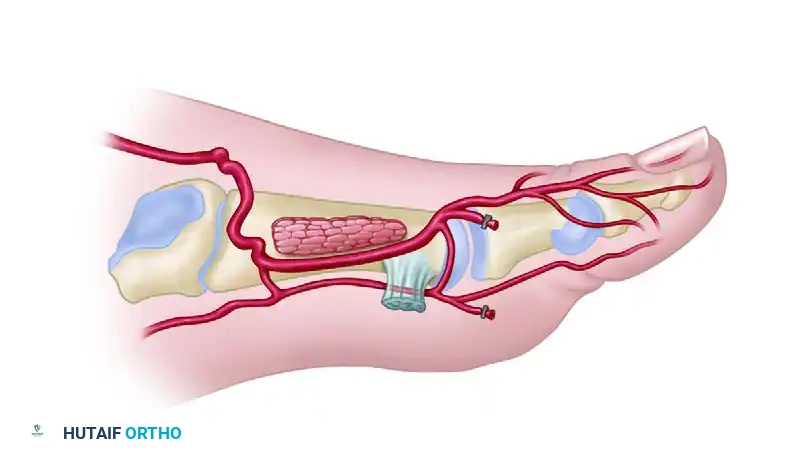

5. Composite Harvest (Optional)

- If vascularized bone is required for the reconstruction, the second metatarsal can be harvested at this stage.

- Perform osteotomies at the proximal and distal metaphyses of the second metatarsal.

- Carefully elevate the bone with the flap, ensuring the periosteal blood supply from the FDMA and DPA is maintained intact.

7. Proximal Pedicle Dissection

- Divide the distal skin margins and the proximal margins near the extensor retinaculum.

- If a long vascular pedicle is required, divide the extensor retinaculum in a Z-shaped fashion. This allows proximal tracing of the DPA into the anterior tibial artery.

- Carefully ligate and divide small side branches (e.g., tarsal arteries) to free the pedicle.